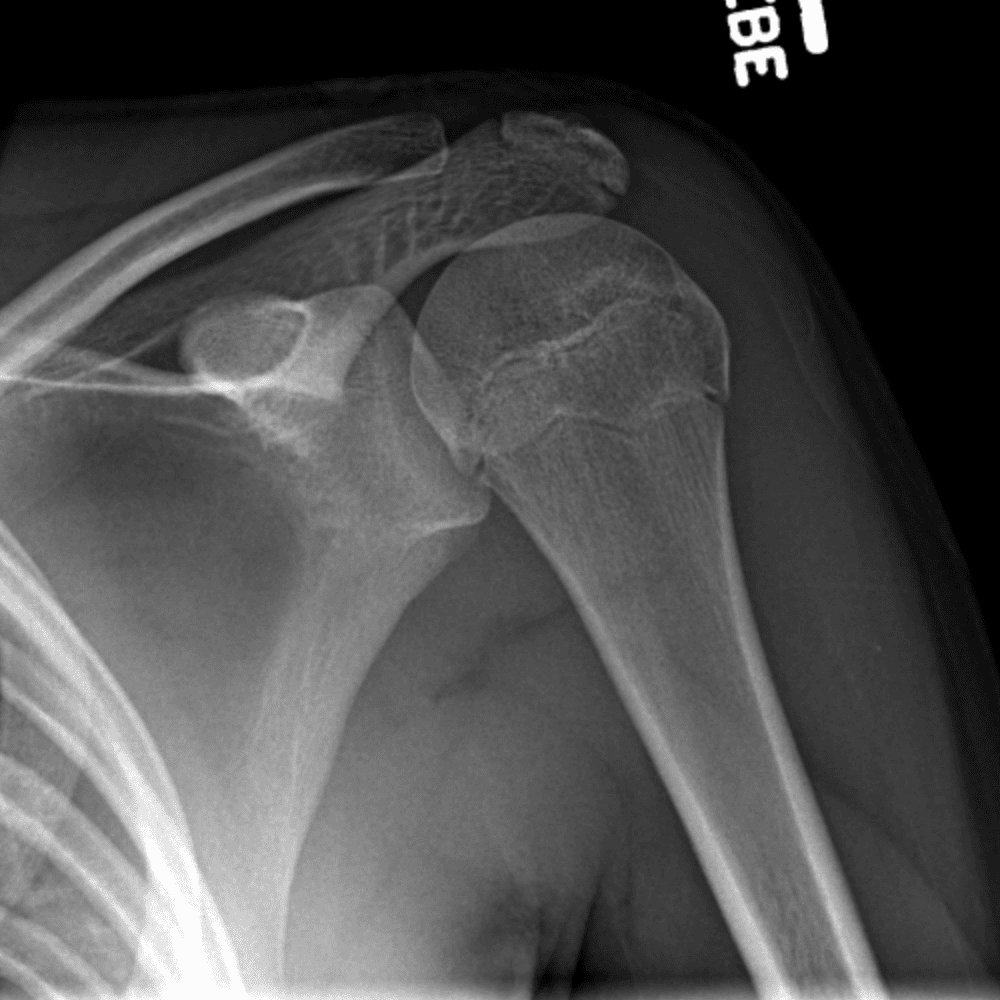

Simuliert den Dienst durch subtile oder schwierige Fälle und einige Normalbefunde.

30 Fälle